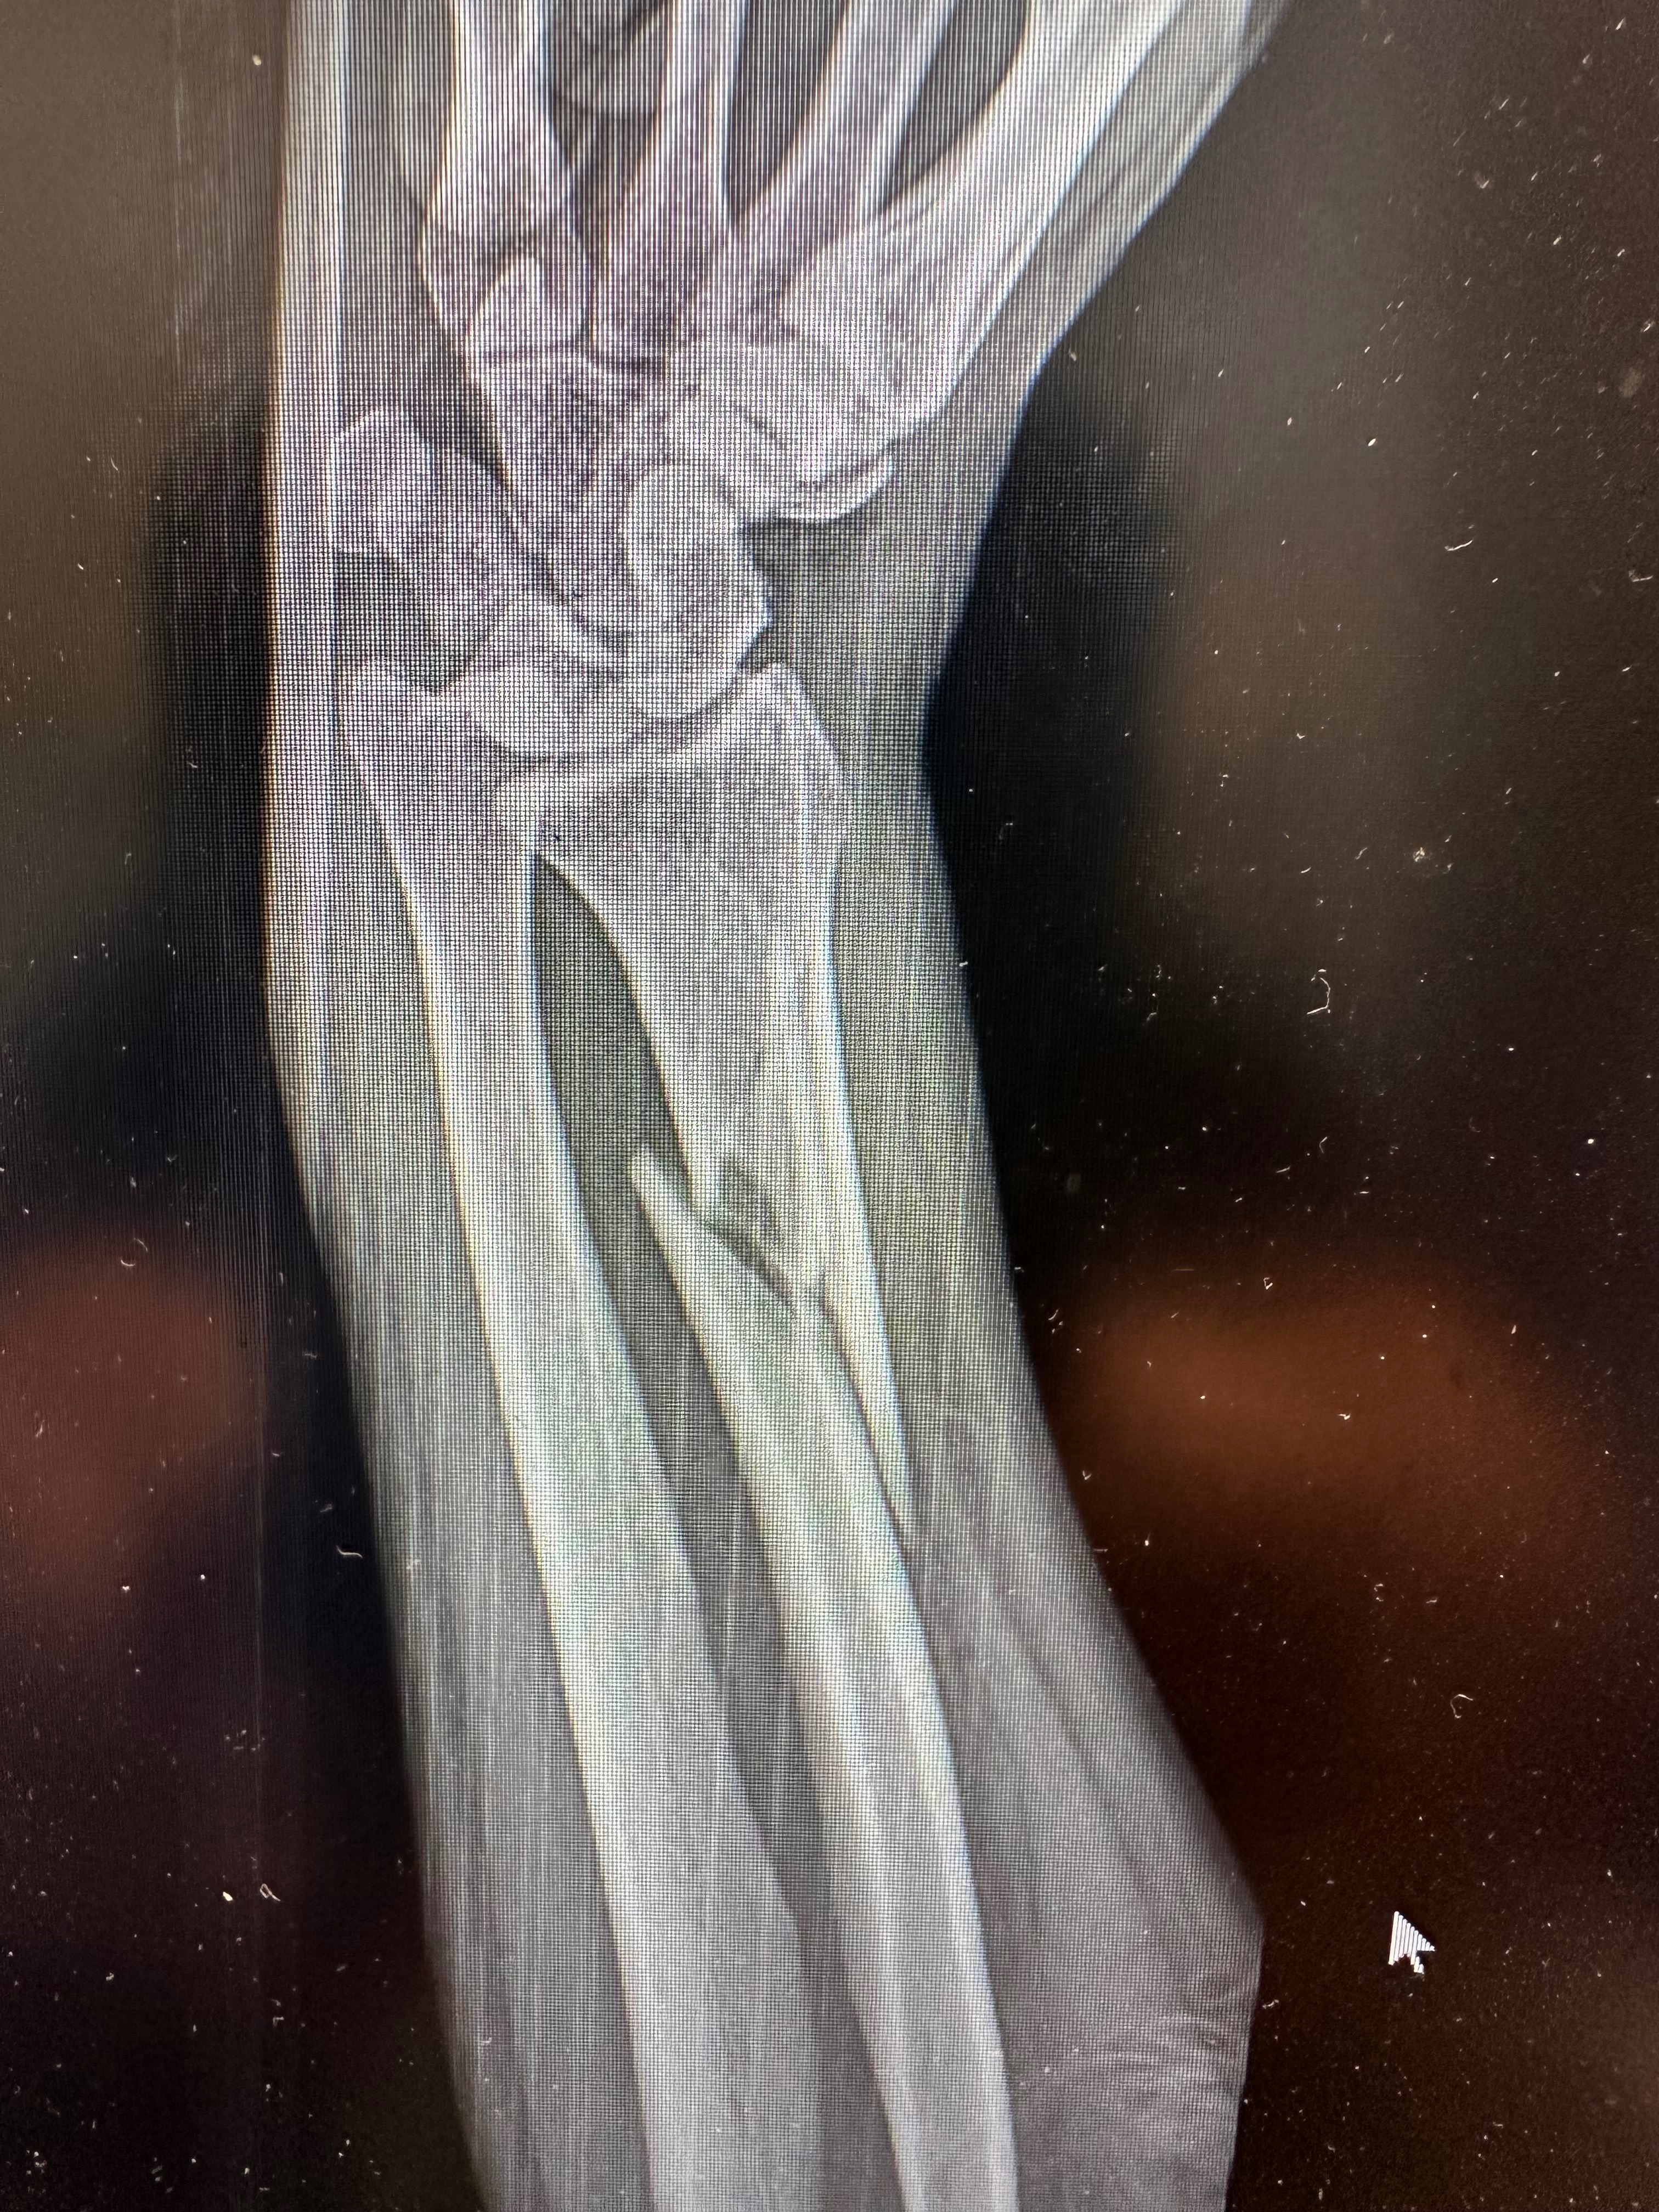

On April 12th, 2024, Alicia was involved in a serious car crash in Bay Roberts, NL. While driving south on Conception Bay Highway, a large truck entered her right of way, causing her to T-bone the vehicle. Her SUV was completely totaled, and Alicia was rushed to Carbonear General Hospital with multiple fractures, including a Galeazzi fracture — a rare and complex arm fracture seen in only 3–7% of all forearm injuries.

The next day, April 13th, 2024, Alicia underwent surgery to repair her arm. Although she has worked incredibly hard through months of rehabilitation, she has regained only about 80% of her range of motion and continues to experience daily pain.